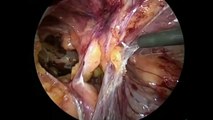

Laparoscopic Hernia Surgery TAPP

This video demonstrates the technique of performing a Laparoscopic hernia repair using TAPP approach, it highlights the important landmarks in this technique as well.